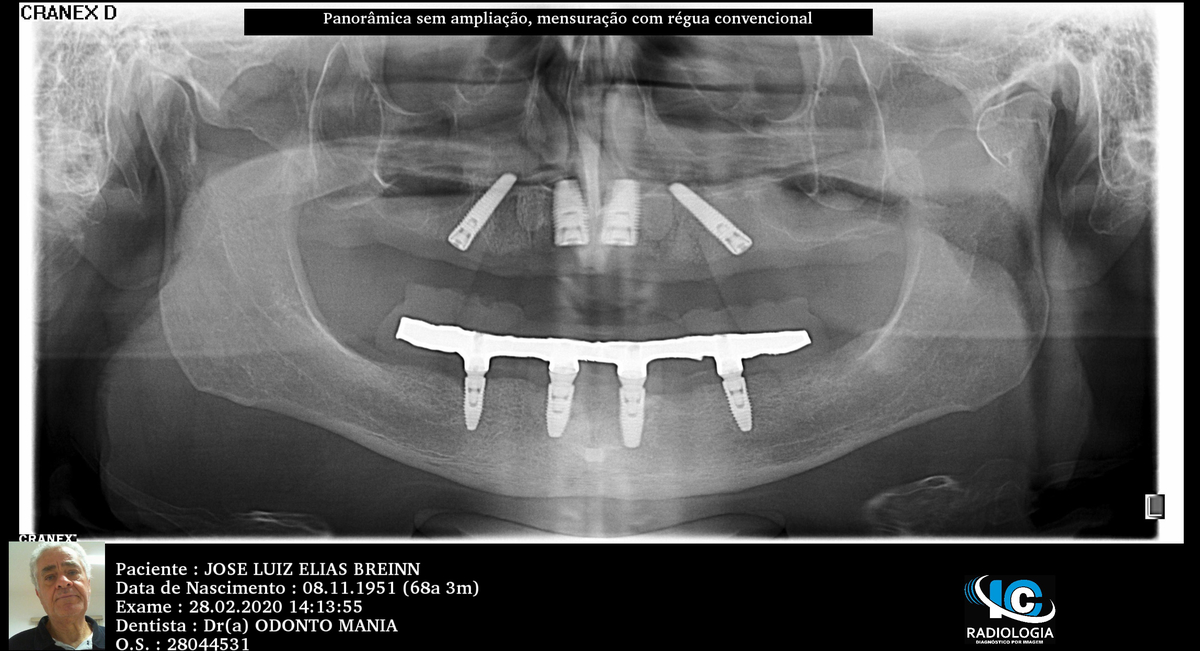

PRÓTESE TOTAL FIXA EM IMPLANTES

J.L.E.B.